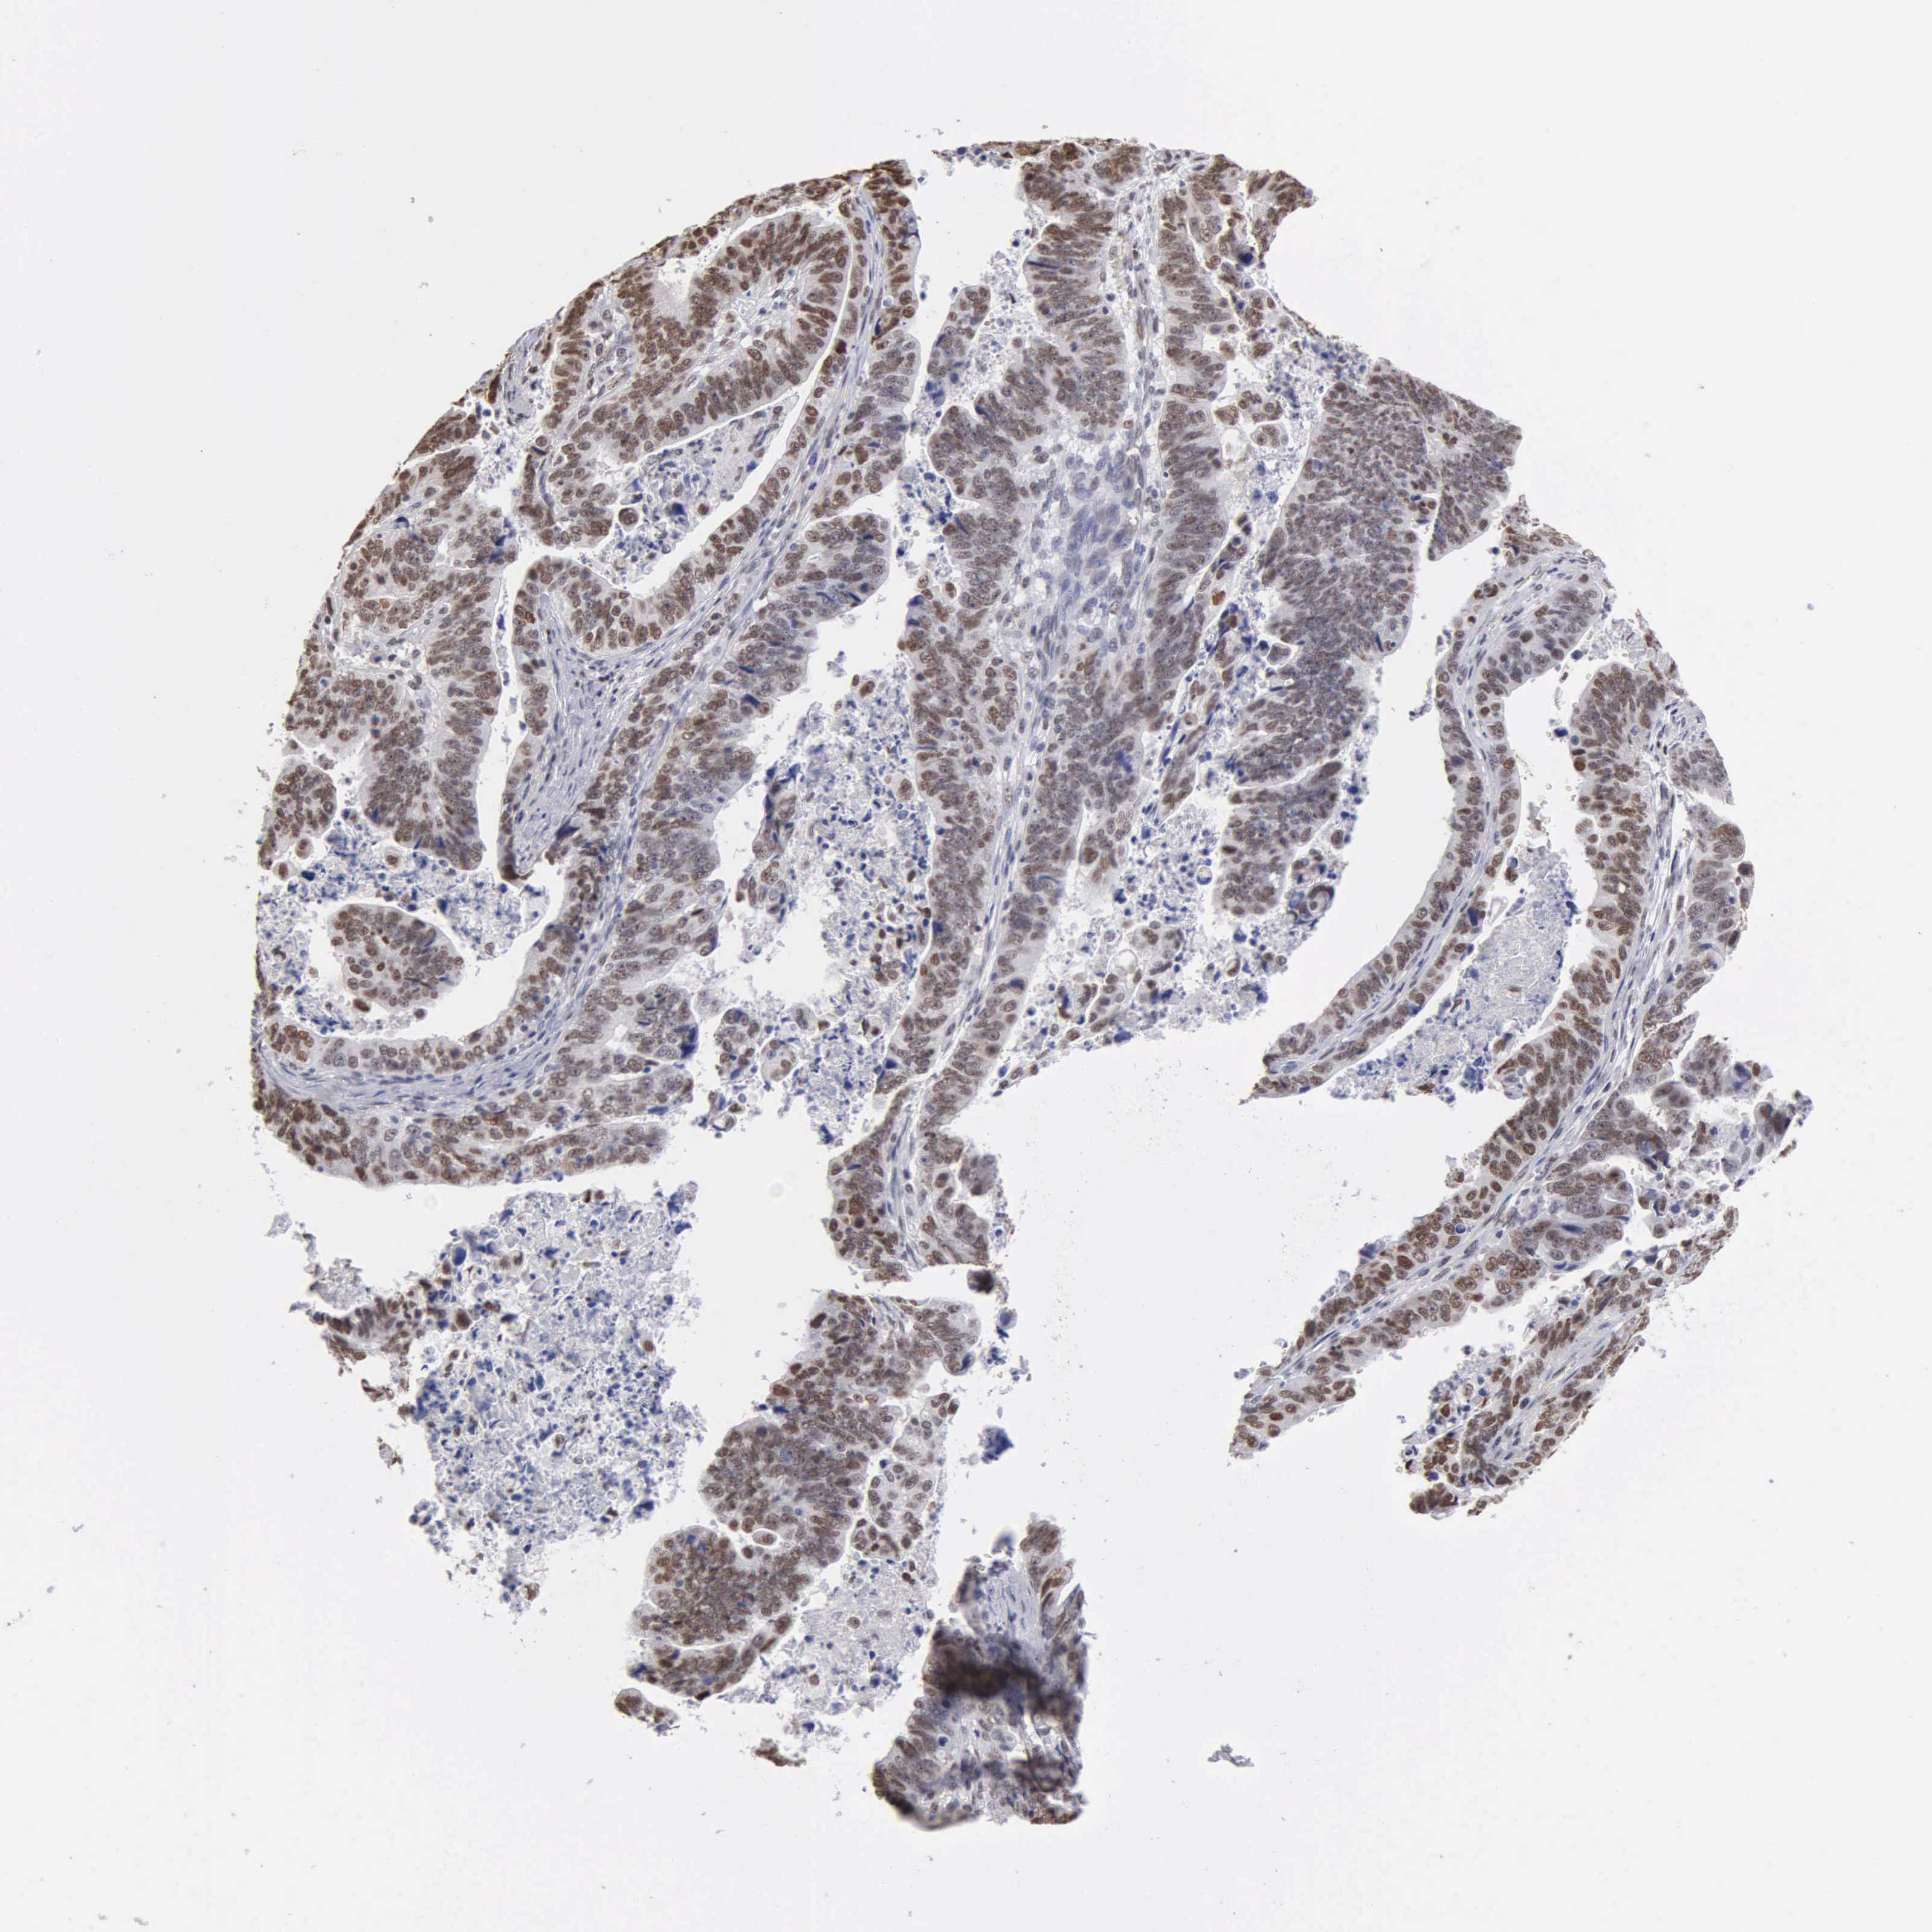

STOMACH CANCER - Protein expressioni

A mouse-over function shows sample information and annotation data. Click on an image to view it in a full screen mode. Samples can be filtered based on level of antibody staining by selecting one or several of the following categories: high, medium, low and not detected. The assay and annotation is described here.

Note that samples used for immunohistochemistry by the Human Protein Atlas do not correspond to samples in the TCGA dataset.

Antibody stainingi

Antibody staining in the annotated cell types in the current human tissue is reported as not detected, low, medium, or high, based on conventional immunohistochemistry profiling in selected tissues. This score is based on the combination of the staining intensity and fraction of stained cells.

Each image is clickable and will lead to virtual microscopy that enables deeper exploration of all samples and also displays staining intensity scores, fraction scores and subcellular localization as well as patient and tissue information for each sample.

Antibody CAB000350

Staining

High

Medium

Low

Not detected

Intensity

Strong

Moderate

Weak

Negative

Quantity

>75%

75%-25%

<25%

None

Location

Nuclear

Cytoplasmic/membranous

Cytoplasmic/membranous,nuclear

Adenocarcinoma, NOS